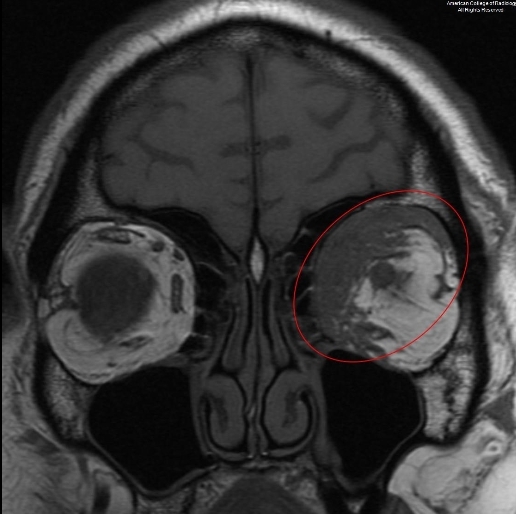

图 3 为平扫冠状压脂 T1 示,左侧眼眶内上方异常信号(椭圆),与周围脂肪不同,病灶压脂后信号并没有降低